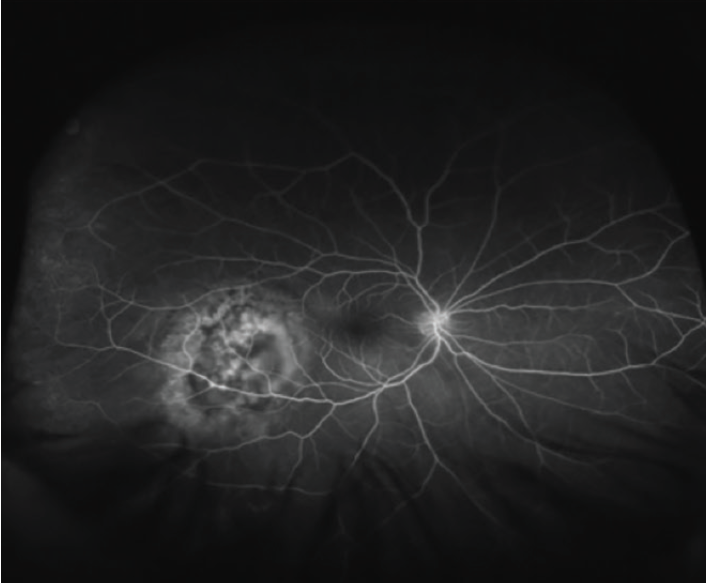

Figure 2. Fluorescein angiography identifies the mass and intact vasculature.

When the patient presented for his ocular oncology appointment, he had not developed any discomfort or pain in his eyes since his appointment with a referring physician that week. His VA was 20/100-1 OD and 20/60+2 in his left eye (OS). Posterior segment evaluation OD was significant for an elevated mass temporal to the macula, 4.5 by 8.0 disc diameters in size. Fundus photography of the lesion highlighted its orange color and size (Figure 1). Fluorescein angiography showed the mass infratemporal to the macula (Figure 2). Ocular ultrasound revealed an elevated posterior pole mass, 12 mm by 14 mm in size, with high internal reflectivity (Figure 3). Ultrasound A-scan demonstrated an area of increased reflectivity (Figure 4). The presumed diagnosis was choroidal metastasis from the patient’s active thyroid cancer.